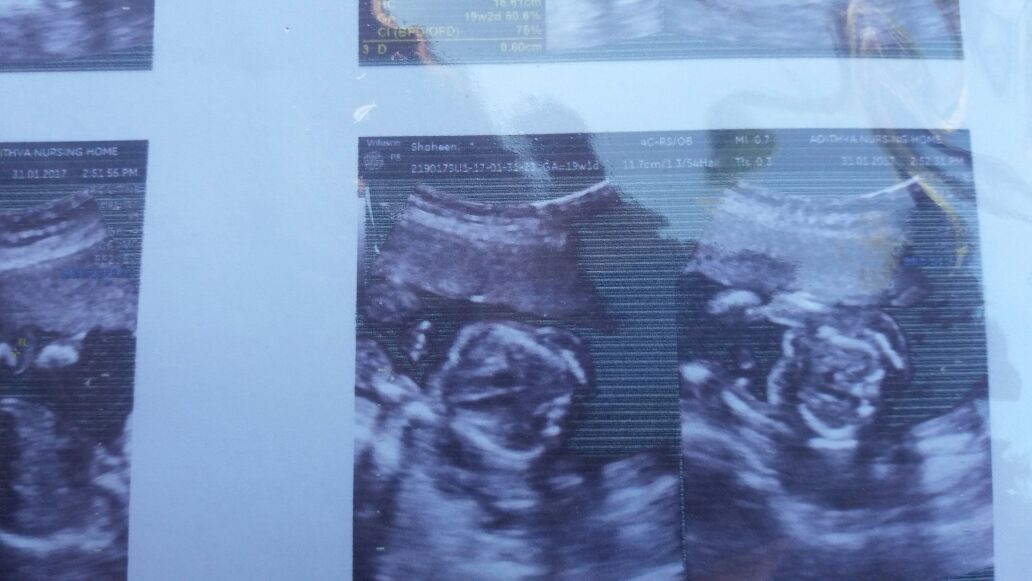

Do you have any potty shots?

Yes I have

Attachment 34783 Attachment 34782

Sorry, no gender showing in these shots. Any 12-14 week side view shots?

No side view shots available,what about 2nd shot in my first post, isn't that a willy?

It could be, but I can't really tell for sure.